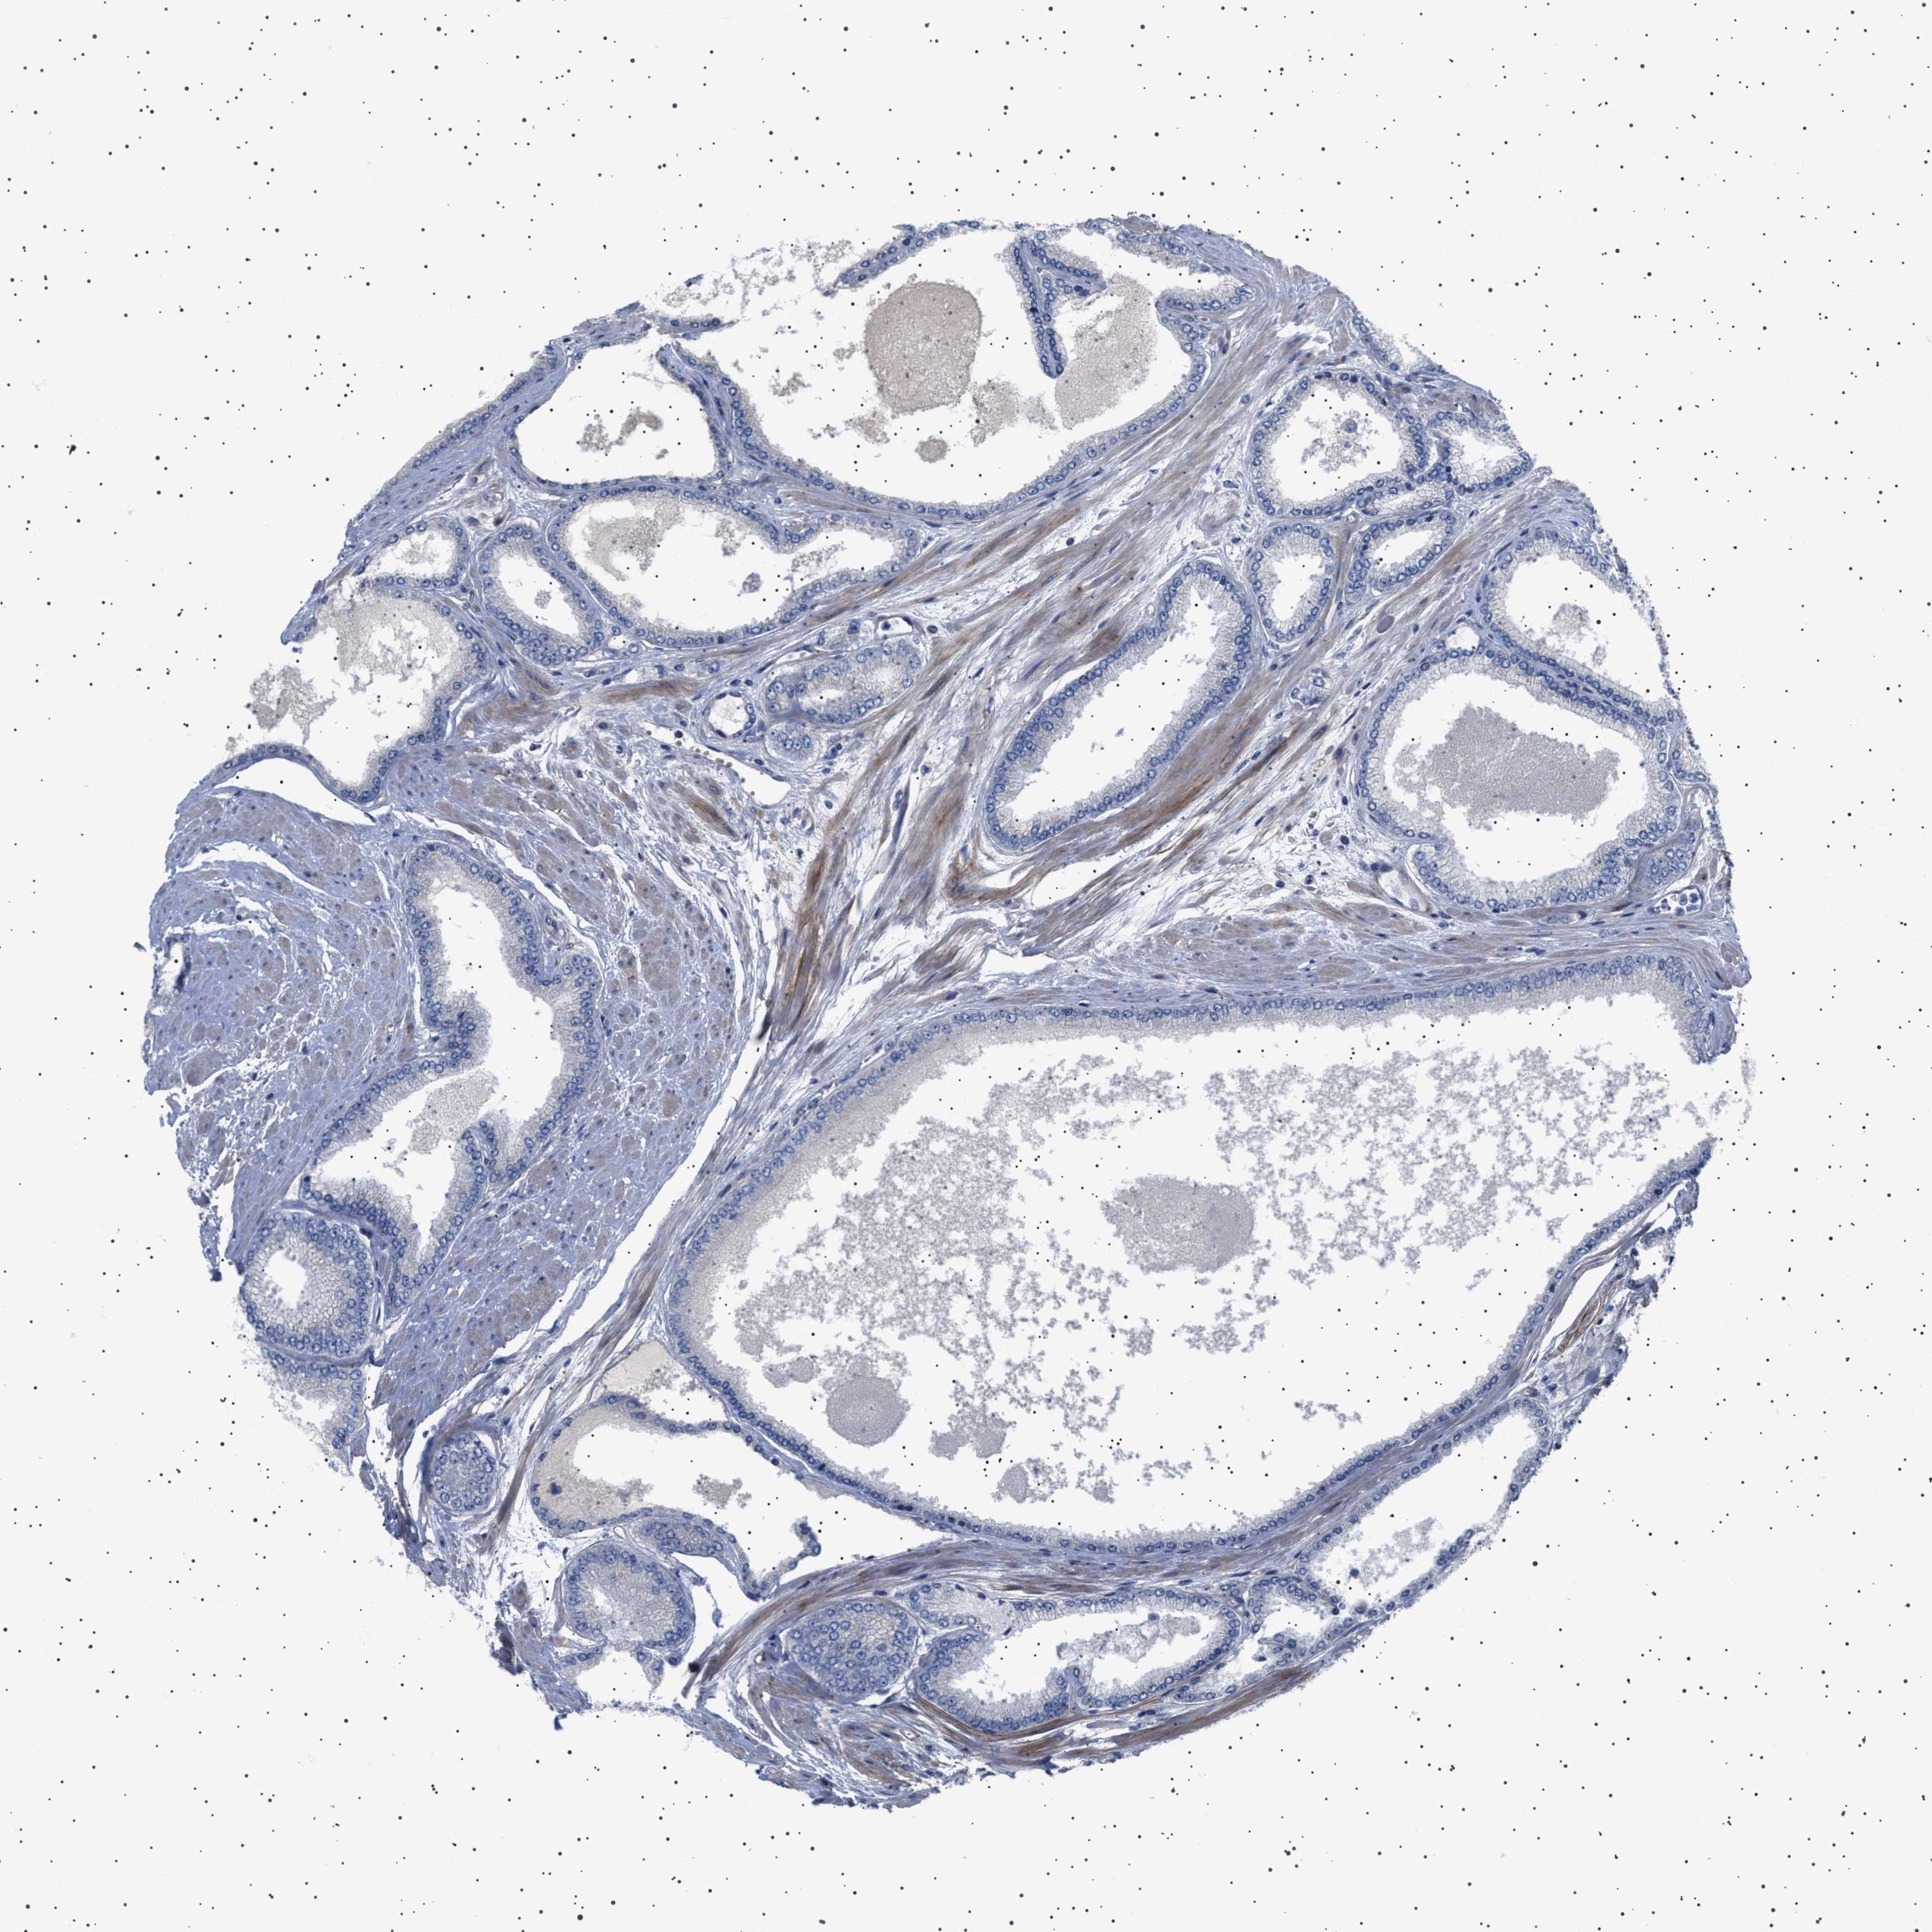

PROSTATE CANCER - Protein expressioni

A mouse-over function shows sample information and annotation data. Click on an image to view it in a full screen mode. Samples can be filtered based on level of antibody staining by selecting one or several of the following categories: high, medium, low and not detected. The assay and annotation is described here.

Note that samples used for immunohistochemistry by the Human Protein Atlas do not correspond to samples in the TCGA dataset.

Antibody stainingi

Antibody staining in the annotated cell types in the current human tissue is reported as not detected, low, medium, or high, based on conventional immunohistochemistry profiling in selected tissues. This score is based on the combination of the staining intensity and fraction of stained cells.

Each image is clickable and will lead to virtual microscopy that enables deeper exploration of all samples and also displays staining intensity scores, fraction scores and subcellular localization as well as patient and tissue information for each sample.

Antibody HPA018073

Staining

High

Medium

Low

Not detected

Intensity

Strong

Moderate

Weak

Negative

Quantity

>75%

75%-25%

<25%

None

Location

Nuclear

Cytoplasmic/membranous

Cytoplasmic/membranous,nuclear

Adenocarcinoma, High grade

Adenocarcinoma, Low grade